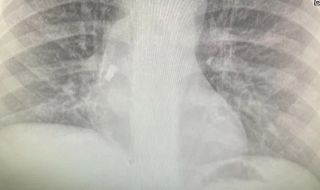

Спасиха дете, след като млечен зъб заседна в трахеята муЛекари спасиха петокласник в Бургас, след като млечен зъб заседна между трахеята и десния бронх на детето и остана там две седмици. Зъбът е паднал ...07.12.20221 7332 -